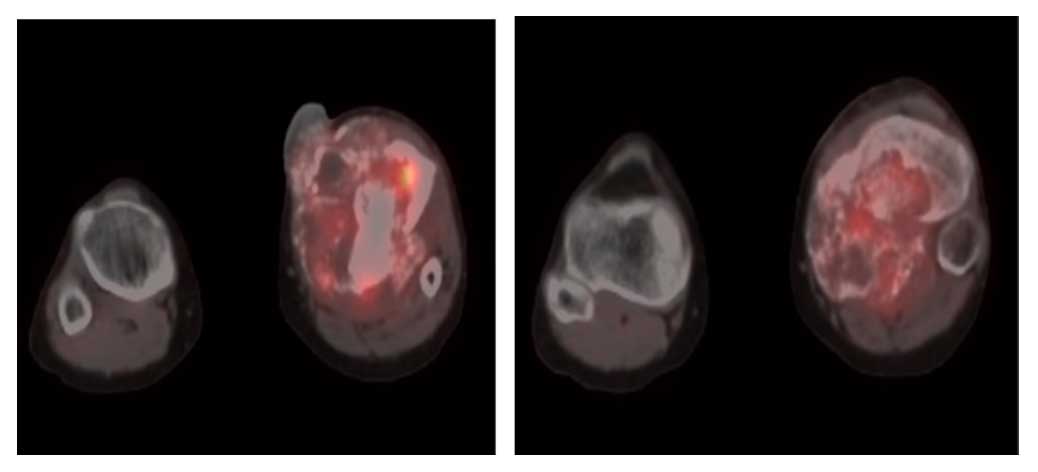

Ameliyat Öncesi: PET-CT’de ciddi harabiyete neden olan, heterojen ve düzensiz sınırlı artmış aktivite gösteren litik ve sklerotik kitle.